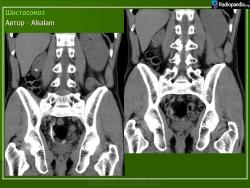

Бильгарциоз (Schistosomiasis) мочевого пузыря